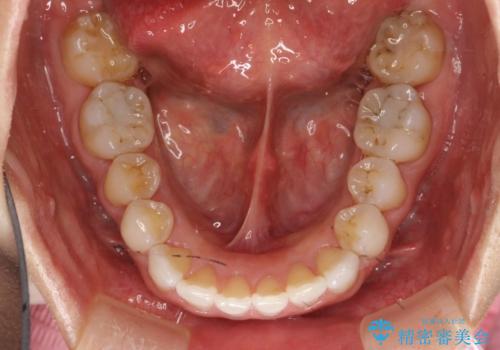

抜歯せずに八重歯のマウスピース矯正

- 非抜歯・遠心移動+IPR+拡大 によるマウスピース矯正を計画した。

八重歯がシビアな場合、抜歯をしないと治せないケースもありますが、奥歯の位置関係を修正したり、歯のサイズダウンを行うことで、抜歯をせずに改善できる場合もたくさんあります。